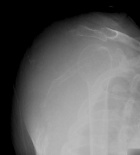

D.C. - 72 year old male with left shoulder pain for six months, recently noted swelling over his scapula

Zoom image: Radiological image Radiological image.